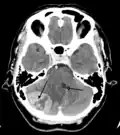

Tumor de la fosa posterior que provoca efecto de masa y desplazamiento del cuarto ventrículo.